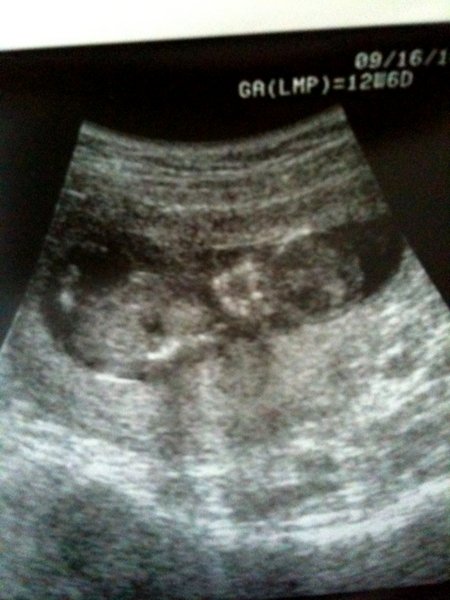

Annyira szep kis fotod van a babakokrol!!!Es a petezsakot korulvevo feher reszt az ngyon jo

Szerintem is megnyugodhatsz ezek a babakok jonnek

Amugy a pontok azok a kis embriok melletti megvilagitott buborekok

Ez a kép Viviről készült, 6hetesen és most is 6 hetes lehetek.

Ez a kép Viviről készült, 6hetesen és most is 6 hetes lehetek.